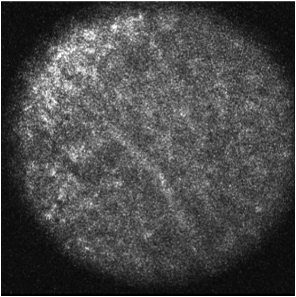

The dataset was collected in a previous study conducted at the University Hospital Schleswig-Holstein in Lübeck where expert assessment of CLM images in the colon area was evaluated ellebrecht2018confocal . A custom intraoperative device with integrated CLM (Karl Storz GmbH & Co KG, Tuttlingen, Germany) was built. The image resolution was pixels which covers a field of view of . In the study, ten rats received colon adenocarcinoma cell implantation in the colon and peritoneum with a growth time of seven days. Then, laparotomy was conducted and images of healthy colon tissue, malignant colon tissue, healthy peritoneum tissue and malignant peritoneum tissue were obtained. Example CLM images for each tissue type are shown in Figure 3. After removal of low quality images, 1577 images remained with 533 belonging to class HC, 309 belonging to class MC, 343 belonging to class HP and 392 belonging to class MP. Note that some subjects are missing classes such that, on average, six subjects per class remain. Ground-truth annotation of all images was obtained by tissue removal of the scanned areas and subsequent histological evaluation.